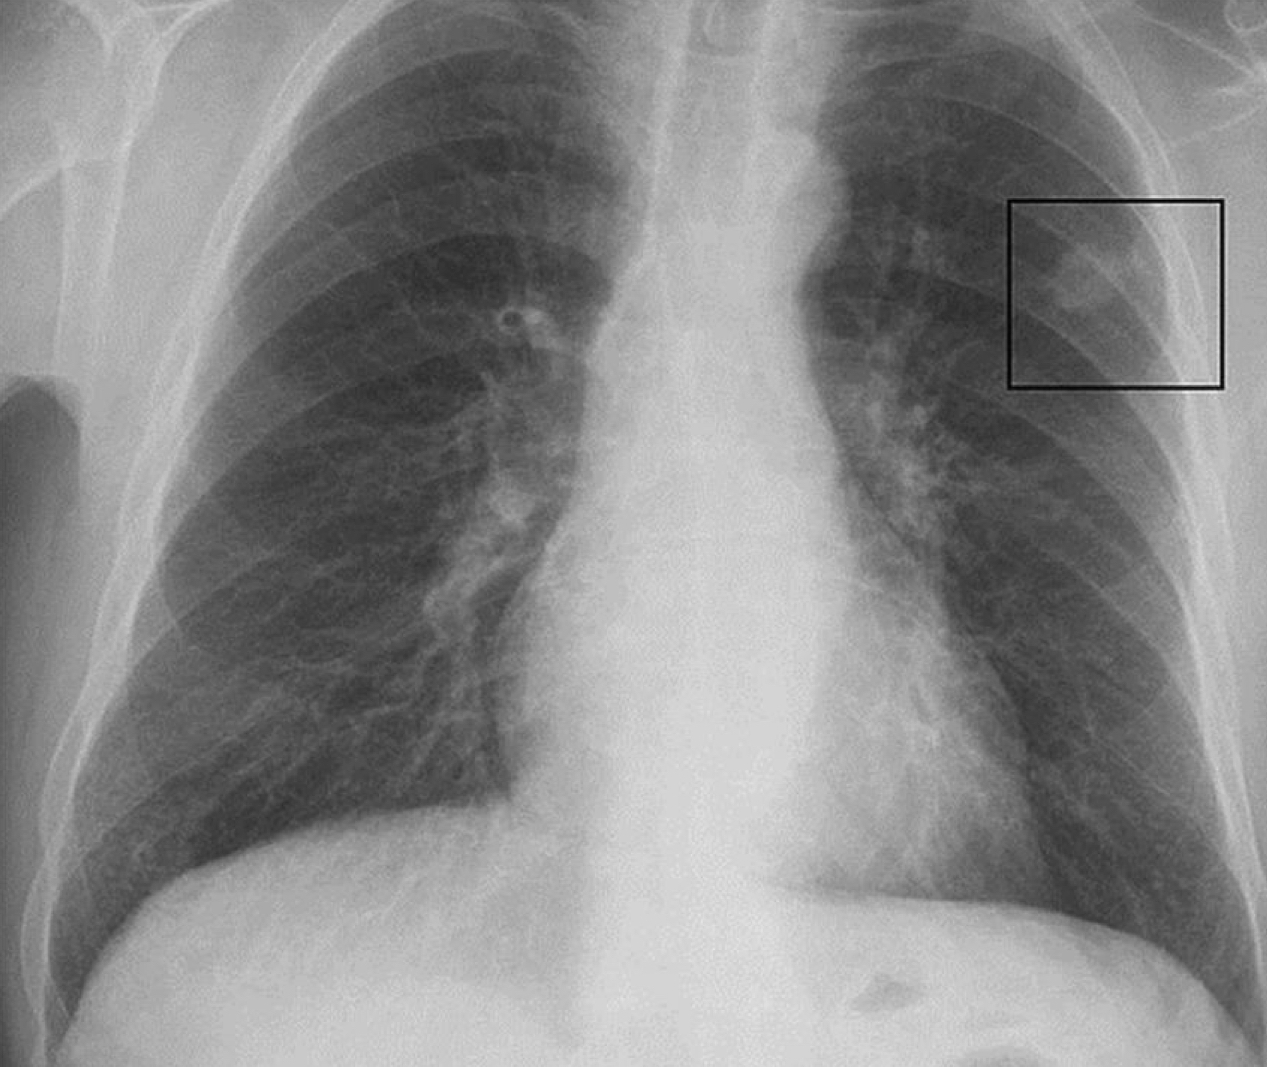

Que se ve ?

A

Nodulo solitario

Promedio= 2.5

común en lob sup